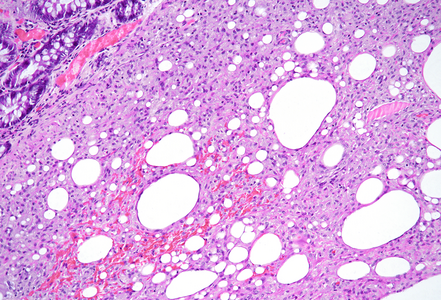

The resection specimen contained superficial remnants of the previously excised tubular adenoma (not shown). Close to the neoplastic glands, however within the submucosa, nodular aggregates of histiocytes were found (Panel A), that included vacuoles of varying size; these vacuoles were mainly empty, except for few tiny droplets of pale fluid or substance (Panels B and C). A CD68 immunostain confirmed histiocytic cell origin (Panel D). Pankeratin staining was negative within the lesion. No atypia was observed, and no eosinophils were present. The histological findings in combination with a history of polypectomy at the same site were consistent with the diagnosis of a “lifting agent granuloma”.